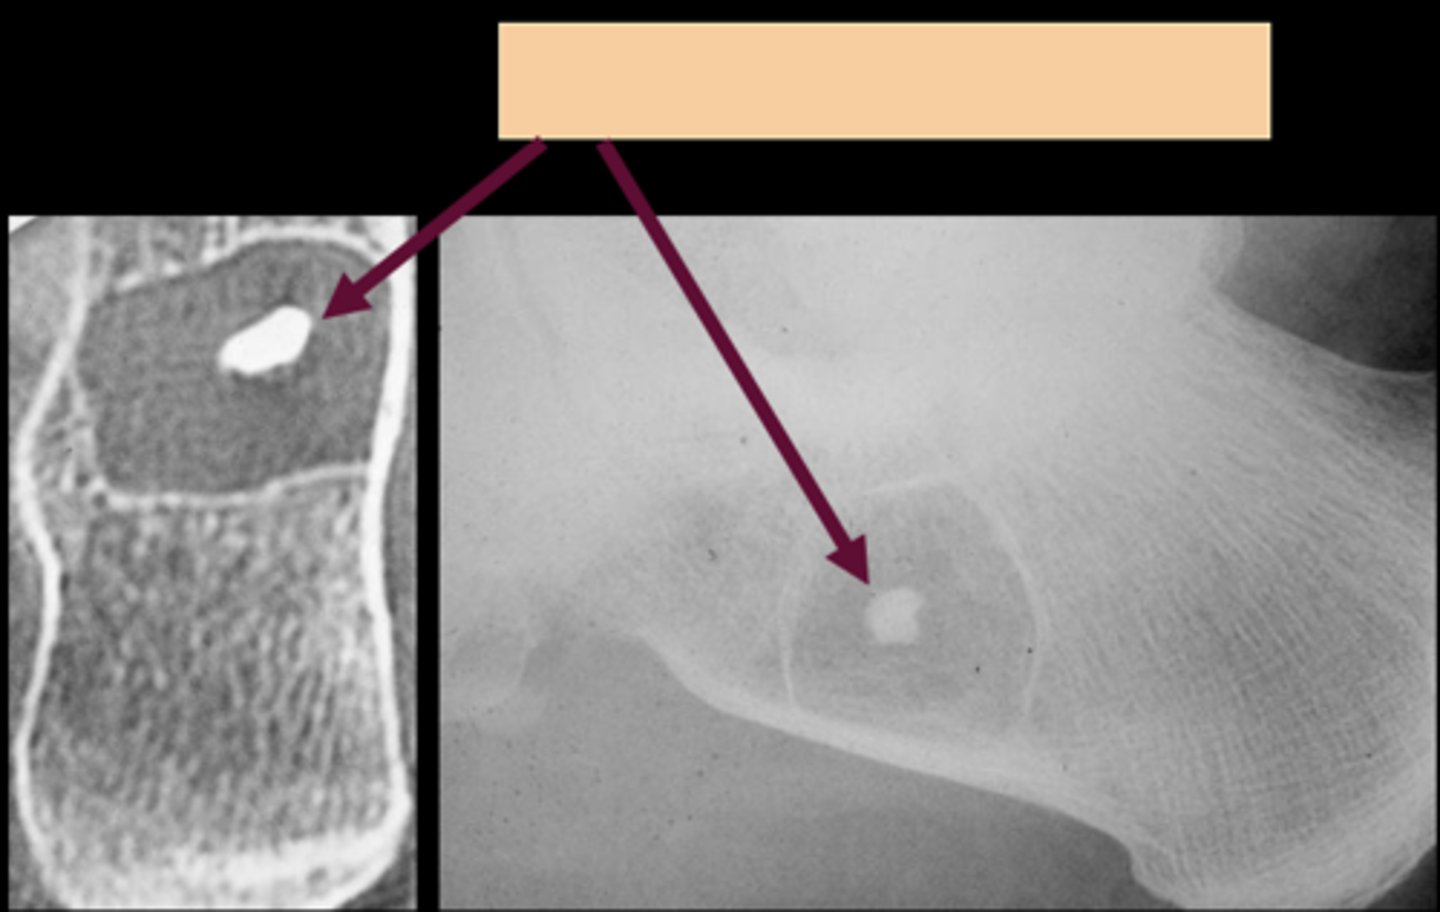

- Asymptomatic

- Central target sequestrum

- Calcaneus

Target sequestrum

ID sign of intraosseous lipoma